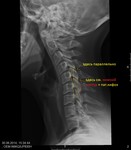

Рентген шоп дуга кифоза

Кифоз шейного отдела позвоночника. В связи с чем может такое происходить? Нужно ли дополнять физиологическими пробами? ![]()

конечно, в идеале надо дополнять функциональными пробами. будет видна нестабильность в сегментах С4-С5, С5-С6, С6-С7.

Кифоз шейного отдела позвоночника. В связи с чем может такое происходить? Нужно ли дополнять физиологическими пробами?

Пробами дополнять можно. Но при согласии пациента на дополнительную дозу.)

действительно 8 позвонков! вижу такое впервые! В моей практике бывают случии (у детей) я описываю их как симптом "кифотической установки" а в заключении пишу: нарушение статики тел шейных позвонков. Если кто не согласен с таким описанием пожалуйста прокоментируйте :) На счет функциональных проб я бы порекомендовал, возможно там будет нестабильность шейных позвонков, то же важный признак.

В протоколе можно описать много всего.)) И нарушение статики, и кифотизацию можно. Главное, в заключение объединить, что возможно. Ведь эти признаки все - за распространённый отдела хондроз.